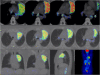

We report a 52-year-old patient who developed B-cell non-Hodgkin's lymphoma subsequent to sarcoidosis. Sarcoidosis was diagnosed 16 years ago and remained asymptomatic for 14 years after steroid treatment. She presented with new symptoms of arthralgia, photosensitivity, butterfly erythema, autoimmune antibodies (ANA, chromatin positivity) associated with progression of the known left upper lobe lesion on the chest X-ray suggesting primary autoimmune disease (systemic lupus erythematosus). As steroid treatment was not effective, we started bolus cyclophosphamide therapy after which progression was seen on the chest X-ray. Computed tomography (CT)-guided needle biopsy confirmed malignancy of indefinable origin. Despite of the well-known fluorodeoxyglucose (FDG) avidity in active sarcoidosis, a FDG-positron emission tomography (PET) scan was performed to stage the primary tumour. Intensive FDG uptake was detected in the affected lung segment, with moderate uptake in mediastinal lymph nodes. The patient underwent left upper lobectomy. The histology showed pulmonary mucosa-associated lymphoma (bronchus-associated lymphoid tissue (BALT) lymphoma) in the lung tissue, while only sarcoidosis was present in the mediastinal lymph nodes. Bone marrow biopsy was negative.The association between sarcoidosis and lymphoma is known as sarcoidosis lymphoma syndrome, which is a rare disease. PET-CT was helpful in the differentiation of sarcoidosis and malignancy in this patient. It is important to be aware of the risk of lymphoma in sarcoidosis and FDG-PET, used for adequate purpose, can help the diagnosis.